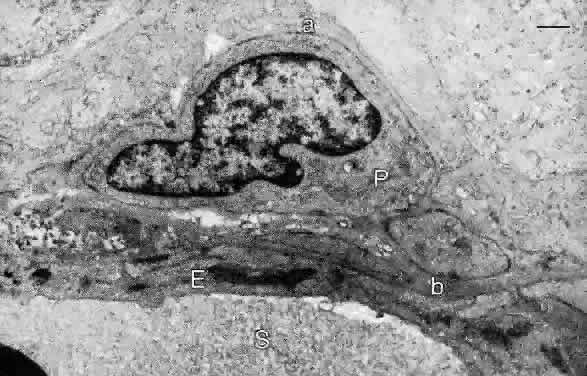

| VASCULAR ELEMENTS |

| The retina has a dual blood supply, and there are two blood—retinal

barriers. The RPE and photoreceptor layers are nourished by the choriocapillaris, whose

endothelial cells are fenestrated and leak serum

proteins that diffuse along the lateral walls of the RPE cells. Tight

junctions between the RPE cells block diffusion of serum components into

the subretinal space and constitute the outer blood—retinal barrier. In

contrast, endothelial cells of the central retinal circulation

lack fenestrations and are joined by zonulae occludentes, forming

the inner blood—retinal barrier. The inner nuclear and ganglion cell layers are supplied by branches of the central retinal artery and vein, which divide to supply the four quadrants of the retina. Within the retina, the main arterial and venous branches lie in the nerve fiber layer and give off arterioles and venules within this layer. The capillaries arising from the arterioles in the nerve fiber layer pass directly into the retina, often at right angles to the vessel of origin. They connect with venous capillaries at all levels in the inner retina. The arterial branches have smooth muscle walls and an endothelium but lack an internal elastic lamina. The branches of the central retinal vein have thin walls of smooth muscle and an endothelium, and the walls of the venules and capillaries contain mural cells (pericytes) enclosed within a basal lamina continuous with that of the endothelial cells (Fig. 19). The endothelial nuclei are oriented along the capillary axis and are long and pale; the mural cell nuclei are small and dense. The peripapillary retina has a distinct group of capillaries forming a network in the nerve fiber layer. These capillaries course along the vessels and nerve bundles, following the arcuate distribution of ganglion cell axons above and below the macula. In the macula, capillaries arise from arterioles off the superior and inferior temporal arteries. These capillaries divide and subdivide at all levels of the inner retina in the macula, except for the fovea, where they are absent in an area 0.25 to 0.6 mm in diameter. As described below, the foveal pit contains only photoreceptors and RPE cells, which are nourished by the underlying choriocapillaris. Lateral displacement of the ganglion cell and inner nuclear layers to the parafovea obviates the need for central retinal vessels within the fovea. This specialization contributes to increased visual acuity in the fovea because blood cells do not circulate between the incoming light and the photoreceptors. |